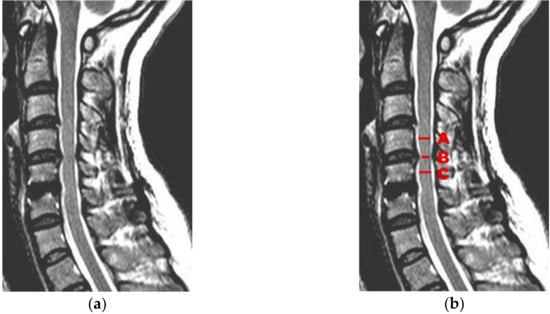

5.6. Medical Example